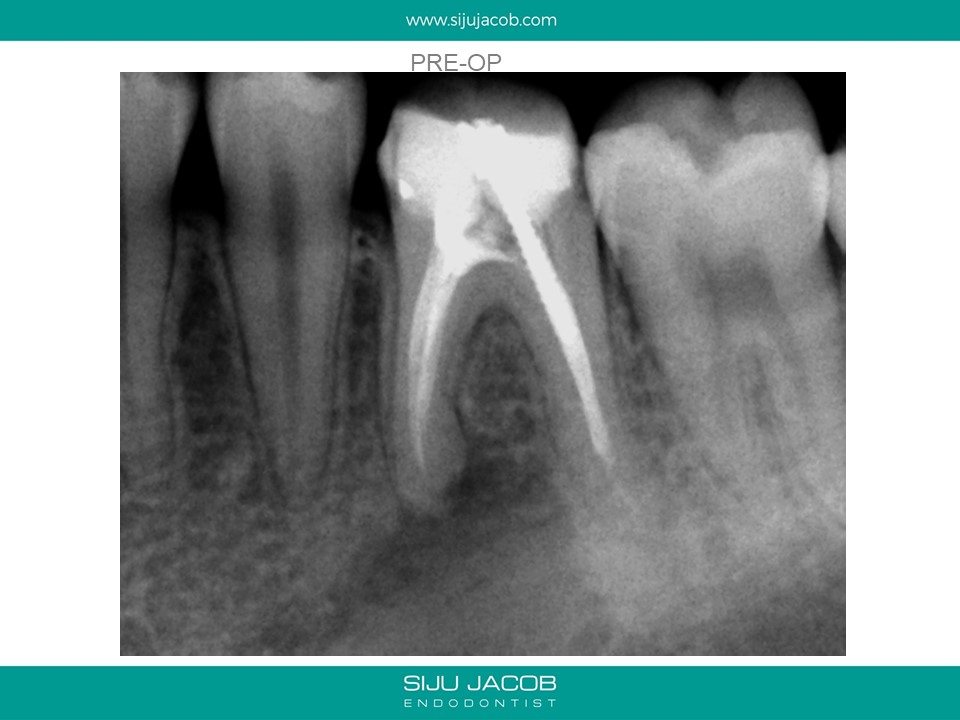

This is a case from 12 years ago. I re-treated all the canals including the distal which had a metal post. At, the one-year recall, the mesial root seems to have healed well. Today, I would probably have left the distal root alone and not over-enlarged those mesial canals.